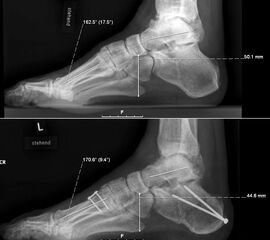

Dorsalflektierende Osteotomien des medialen Mittelfuβes (Abb. 6 – 9, Video 4)

Generell wird die dorsalflektierende MT I Osteotomie (Abb. 6 und 7) nicht isoliert ausgeführt, sondern ist Teil der gesamten Hohlfuβ-Korrektur. Beim absolut flexiblen Hohlfuβ ist sie gelegentlich zusammen mit einem Peroneus longus auf brevis oder einem Release der Plantarfaszie ausreichend. Diese Osteotomie ist einfach durchzuführen und hat eine geringe Pseudarthroserate.

Eine ähnliche dorsalflektierende Osteotomie des Os cuneiforme mediale (reversed Cotton Osteotomie, Abb. 8 und 9), ebenfalls mit Entnahme eines dorsal basierten Knochenkeils, ist effektiver im Ausmass der Korrektur, jedoch oftmals wegen der Insertion des kräftigen Lisfranc-Ligaments nur schwierig zu schliessen.

Sind nicht nur der Strahl I, sondern auch die Strahlen II und III deutlich plantarflektiert, sollte auch hier analog eine dorsalflektierende Osteotomie durchgeführt werden um eine Transfermetatarsalgie zu vermeiden. In der präoperativen klinischen und radiologischen Untersuchung sollte dies bereits antizipiert und intraoperativ verifiziert werden.